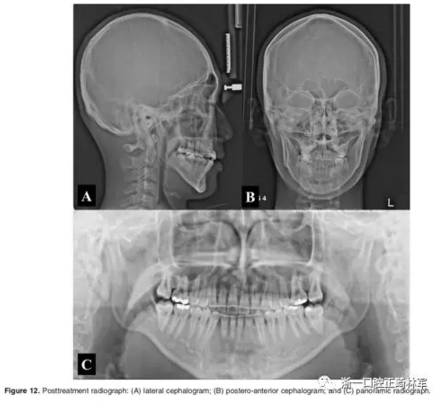

影像學(xué):頭顱側(cè)位片示:矢狀向和垂直向骨骼發(fā)生變化(ANB角,3°;SN-MP,51°);上頜切牙略前傾(U1-SN,106°),與下頜切牙一致(IMPA,75°);病人的面部輪廓得以保持。全景片示:由于牙齒萌出,上前牙區(qū)垂直向牙槽骨水平增加;雖然前牙牙根較彎曲,但其平行度仍可,且無(wú)明顯的牙根吸收。CBCT示:前牙唇側(cè)骨質(zhì)連續(xù)性改善,牙根唇側(cè)支持組織變好,牙槽骨高度、厚度均有增加,但轉(zhuǎn)矩的改變一定程度上導(dǎo)致了局部應(yīng)力的增大。